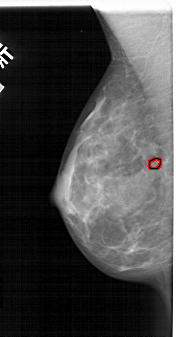

A_1841_1.RIGHT_CC

RIGHT_CC LINES 4936 PIXELS_PER_LINE 2461 BITS_PER_PIXEL 12 RESOLUTION 43.5 NON_OVERLAY

FILE: A_1841_1.LEFT_CC.OVERLAY

TOTAL_ABNORMALITIES 1

ABNORMALITY 1

LESION_TYPE CALCIFICATION TYPE PLEOMORPHIC DISTRIBUTION CLUSTERED

ASSESSMENT 4

SUBTLETY 1

PATHOLOGY BENIGN

TOTAL_OUTLINES 1

BOUNDARY